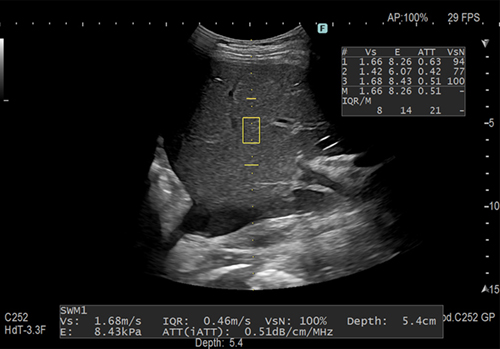

「Shear Wave Measurement(SWM)/iATT」搭載

せん断弾性波の伝搬速度(Vs)を計測することで硬さを評価できます。「ATT(iATT)」は超音波の減衰量を非侵襲的に計測し,肝臓の脂肪量を定性的に評価する為の情報を提供します。